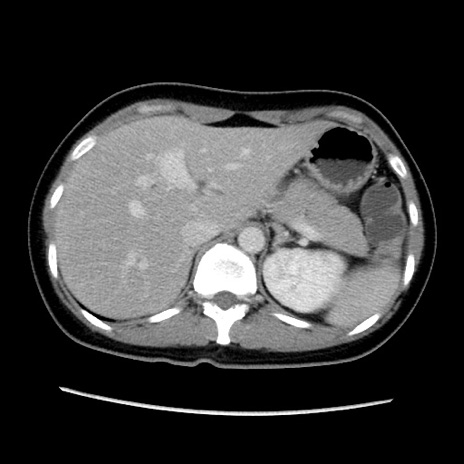

症例39(横断像)

【症例】40歳代女性

【主訴】上下腹部痛

【現病歴】2日目から下腹部痛あり。夜間は痛みで眠れなかった。昨日より上腹部痛と下痢が出現。臥位で痛みは軽快したため、休んでいた。本日になって臥位でも立位でも痛みが強くなってきたため救急要請。

【既往歴】子宮内膜症

【身体所見】部:平坦・軟、左上下腹部に圧痛あり、反跳痛あり。

【データ】WBC 21800、CRP 26.78